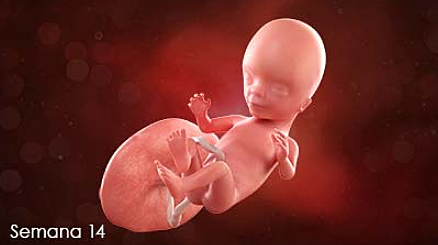

• Semana de la 13 a la 14

Semana de la 13 a la 14

El bebe en estas semanas ya se le podrán ir formando mejor los órgano y su cabeza todavía no tendrá forma ,aunque en estas semanas ya comenzara a funcionar el sistema nervioso y pesara 20 a 25 gramos, medirá de 7 o 8 cm